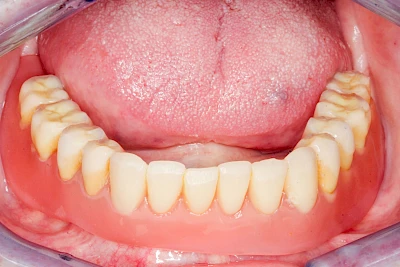

Fehlen einzelne Zähne und die Nachbarzähne sind unbeschadet oder gut zahnärztlich versorgt, werden immer häufiger Implantate gewählt, um die Lücken zu schließen. Auch bei größeren oder verteilten Lücken, wenn keine herausnehmbare Prothese gewünscht ist, werden Implantate für Kronen- bzw. Brückenversorgungen gesetzt. In Einzelfällen entscheiden sich sogar zahnlose Patienten für eine festsitzende Versorgung auf Implantaten.

Varianten zur Verankerung von festsitzendem Zahnersatz auf Implantaten

Implantate: Prothesen